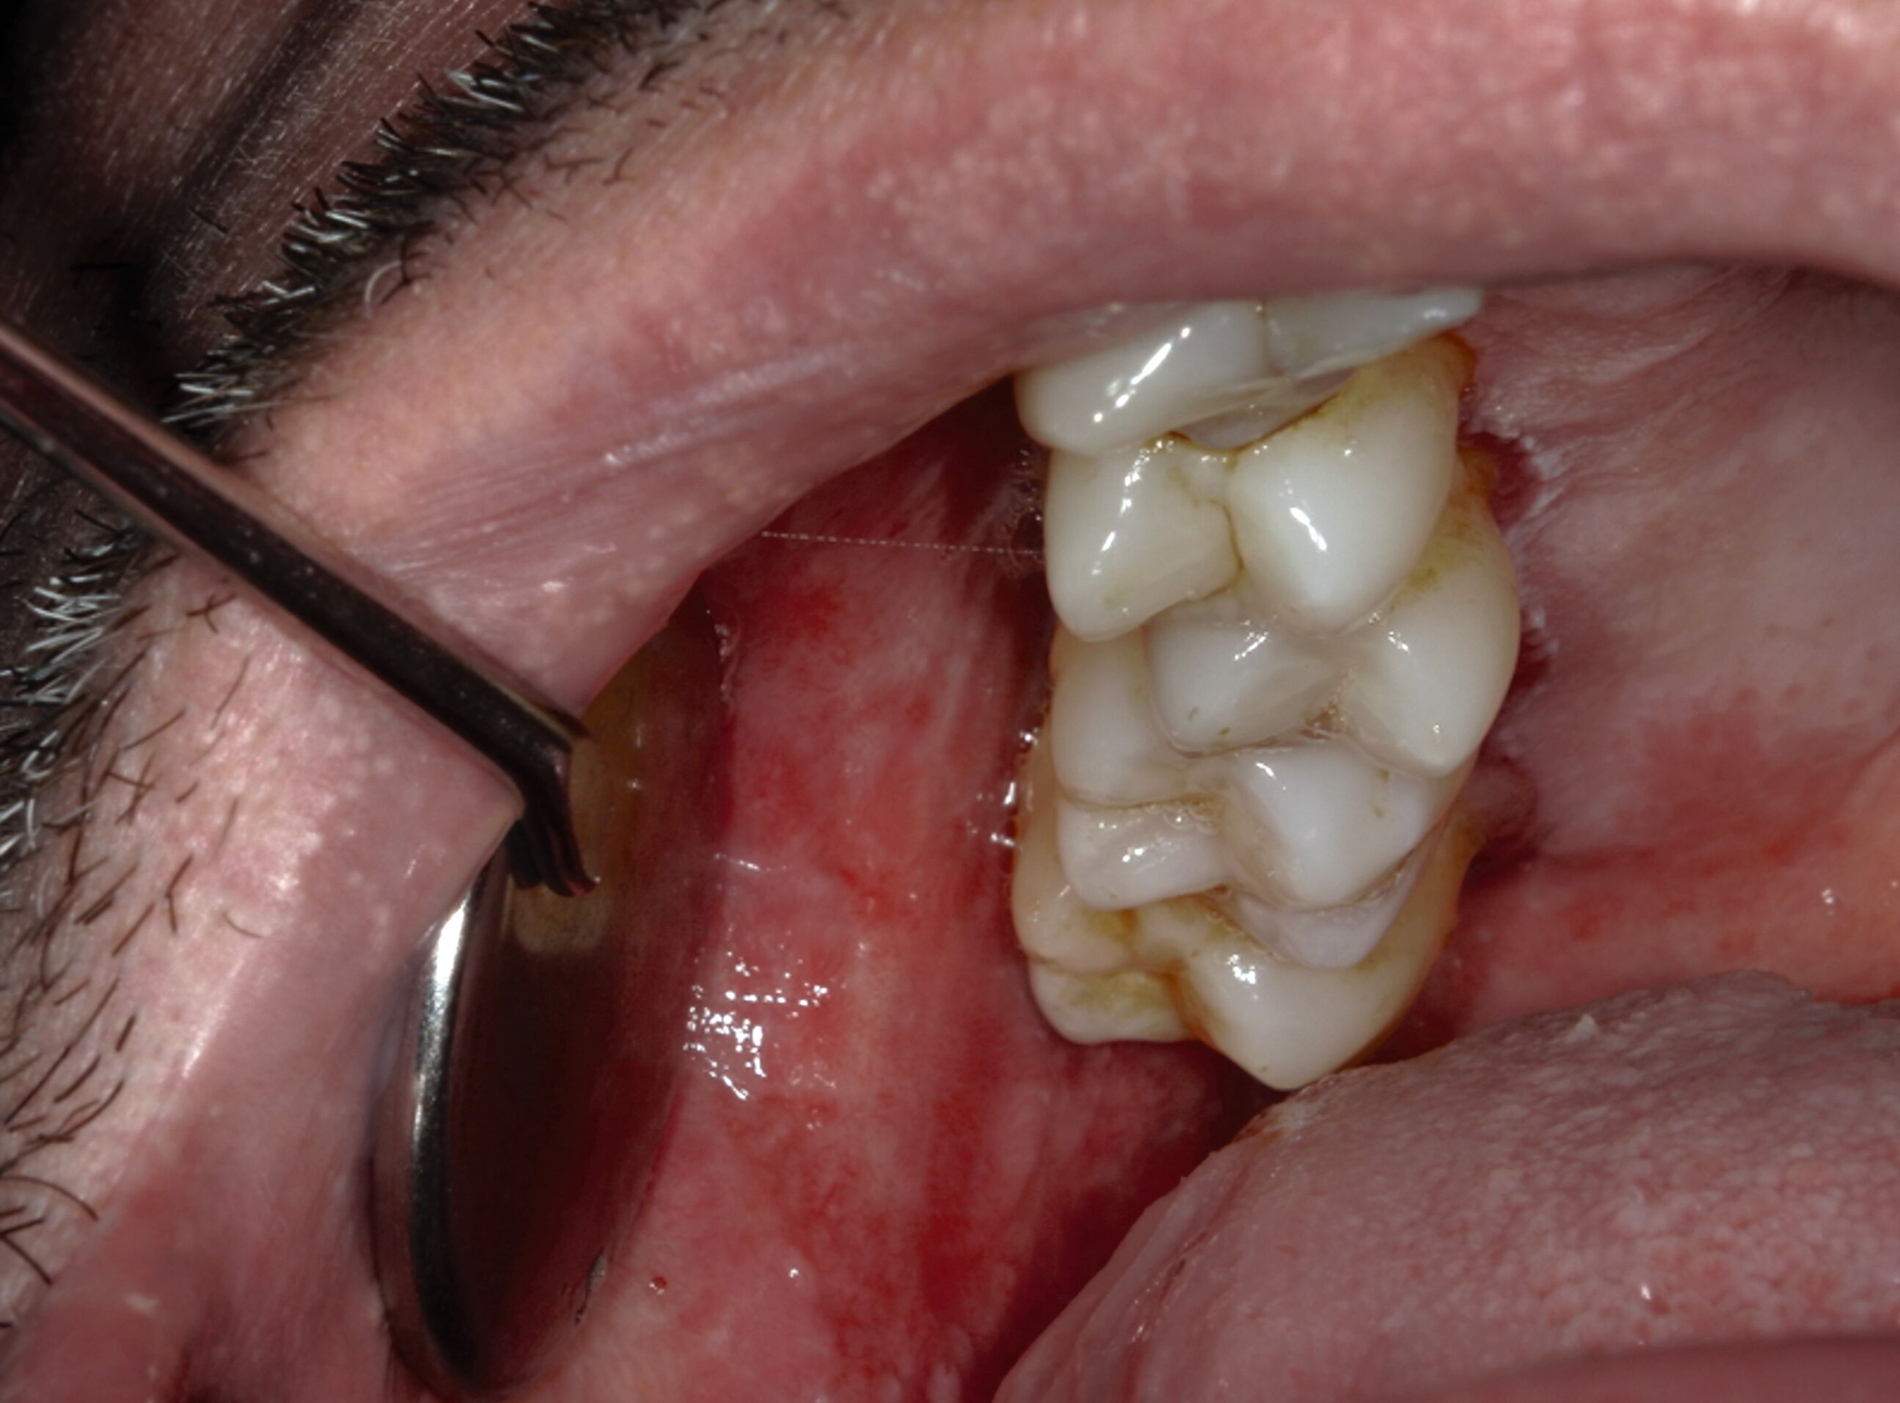

Der OLP manifestiert sich typischerweise durch weiße, netzartige Streifen (Wickham-Striae; Abbildung 6) und kann retikuläre (Abbildung 2), plaqueartige, papuläre, atrophische/erosive (Abbildung 3), ulzerative und bullöse Formen annehmen. Die häufigste Form des OLP ist die retikuläre Form, die sich durch ein netzartiges Muster auszeichnet. Alle Formen können schmerzhafte Ulzerationen und Erosionen umfassen, die das Essen und das Sprechen beeinträchtigen [Mansouri et al., 2024]. OLP-Läsionen treten häufig symmetrisch auf der buccalen Mukosa, der Zunge, den Lippen, der Gingiva, dem Gaumen und selten am Mundboden auf. Diese charakteristischen Merkmale können in der Regel durch eine visuelle Inspektion und die Anamneseerhebung identifiziert werden [Piyarathne et al., 2024]; bei Bedarf kann eine Bestätigung mittels Biopsie durchgeführt werden.

Fortgeschrittene Fälle weisen häufig kompliziertere klinische Merkmale auf und können durch eine stärkere Immunreaktion sowie das Vorhandensein von erosiven und atrophischen Läsionen gekennzeichnet sein. Oft ist eine detaillierte histopathologische Untersuchung erforderlich, um die Diagnose zu bestätigen und präkanzeröse/maligne Veränderungen auszuschließen. Immunhistochemische Tests können zusätzliche Informationen liefern und die Diagnose unterstützen. Differenzialdiagnosen umfassen Candida-Infektionen, Leukoplakie, Pemphigus vulgaris und andere autoimmunbedingte Erkrankungen. Wichtig bei einer solchen bioptischen Sicherung der Diagnose sind dabei die korrekte Auswahl der Biopsiestelle und die adäquate Handhabung des Gewebes, um ausreichend Material für die histopathologische Untersuchung zu gewinnen [Liu et al., 2024]. Das Risiko, ein orales Karzinom mittels einer Inzisionsbiopsie einer potenziell malignen Mundschleimhautveränderung zu übersehen, beträgt laut klinischen Studien sieben bis zehn Prozent [Chiesa et al., 1986; Holmstrup et al., 2007]. Insofern ist für die optimale diagnostische Sicherheit – wenn möglich – stets die Exzisionsbiopsie anzustreben [Hertrampf et al., 2019]. Bei stark auf Malignität verdächtigen Läsionen sind die Biopsie und die Gewebsuntersuchung optimalerweise an der für die spätere Therapie verantwortlichen Fachklinik durchzuführen. Die Anforderungen an die Skalpellbiospie (Abbildung 7) sind so komplex, dass sie in der zahnärztlichen Praxis oft nicht erfüllt werden können.